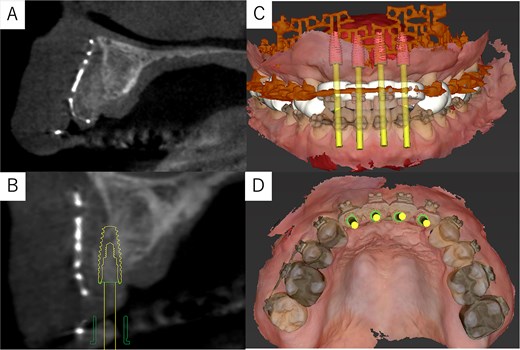

The postoperative panoramic radiograph showed no abnormalities (Fig. 4C). Cone-beam computed tomography images taken 2 months after surgery confirmed the stability of the grafted bone (Fig. 5A). A new simulation for dental implant placement was performed (Fig. 5B–D). At 4 months postoperatively, the titanium mesh was removed, and dental implants were placed. Bone tissue in the defect was confirmed. Implants with a diameter of 4.1 mm and a length of 10 mm (Straumann BLT/RC; Straumann, Basel, Switzerland) were successfully inserted (Fig. 6A–C). Postoperative photographs (Fig. 7) showed improvement in the skeletal mandibular protrusion and a favorable intermaxillary relationship between the upper and lower jaws.

Post-surgery cone-beam computed tomography and implant simulation. (A) Cone-beam computed tomography at 2 months postoperatively confirmed grafted bone stability. (B) Simulation of dental implant placement with a sagittal cross-sectional cone-beam computed tomography image. (C) Frontal view of implant placement. (D) Occlusal view of implant placement.